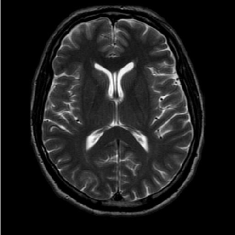

Figure 2: Test Images.

We turn now to test TDIHT for high dimensional signals. We test the performance of several MRI images: the Shepp-Logan phantom, FLAIT brain image, T2 Sagittal view of the lumbar spine and the circle of Willis. The first image is of size 256×256256256256\times 256, while the other are of size 512×512512512512\times 512. They are all presented in Fig. 2.

We focus on the recovery of these images from a few number of Fourier measurements. With 𝛀𝛀{\mathbf{\Omega}} set to be the undecimated Haar transform with one level of resolution (redundancy four) and 𝐃𝐃\mathbf{D} its inverse transform, we succeed to recover the phantom image using only 181818 sampled radial lines, which is only 6.5%percent6.56.5\% of the measurements. This number is only slightly larger than the number needed for GAP, relaxed ASP (RASP) and Relaxed ACoSaMP (RACoSaMP) in [10, 38]. The advantage of TDIHT over these methods is its low complexity as it requires applying only 𝐌𝐌{\mathbf{M}} and its conjugate and 𝛀𝛀{\mathbf{\Omega}} and its inverse transform while in the other algorithms a high dimensional least squares minimization problem should be solved. Note also that for AIHT and RAHTP the number of radial lines needed for recovery is 353535 and for IHT (with the decimated Haar operator with one level of resolution) we need more than 505050 radial lines.

Method FLAIT Brain Lumber Spine The Circle of Willis

Noiseless Noisy Noiseless Noisy Noiseless Noisy

Naive 31.7 31.3 34.5 33.3 30 29.6

TDIHT 43.9 39.2 42.2 36.6 38.2 34.8

RASP 41.3 36.2 39.9 36.5 34.3 33.2

GAP 42.1 35.8 40.4 34.6 36.2 32.7

Table 1: Recovery of FLAIT brain from var. dens. 1 samples, lumber spine from var. dens. 2 samples and circle of Willis from var. dens. 1 samples in the noiseless and noisy (with SNR 20) cases. The reconstruction quality is measured by PSNR.

We perform similar experiments for the other images. Instead of uniformly sampling radial lines, we use pseudo-random variable-density undersampling patterns [62]333Unlike [62] we perform our experiments with real (non-complex) images. The sampling patterns we use can be downloaded from http://www.eecs.berkeley.edu/similar-to\simmlustig/CS.html. presented in Fig. 4. We use var. dens. 1 with FLAIT brain and the circle of Willis and var. dens. 2 with lumber spine.

As the images at hand are only approximately cosparse, we set a threshold, 0.010.010.01 in the noiseless case and 0.050.050.05 in the noisy one, such that each element in the cosparse representation below it is considered as zero. These thresholds create a model error in the recovery but provide a larger cosparsity value that eases the recovery. Moreover, in the noisy case, it is natural to set such a threshold since anyway small representation coefficients are being covered by the noise.

Table 1 summarizes the recovery performance, in terms of PSNR, for the FLAIT brain, lumbar spine and circle of Willis images both for the noiseless and noisy cases. To evaluate the performance of TDIHT in the noiseless case, we compare its PSNR with the one of the model error (which we get by applying 𝛀𝛀{\mathbf{\Omega}} on the original image followed by thresholding and multiplication by 𝐃𝐃{\bf D}). For FLAIT brain and lumber spine we get errors, which are comparable, and even better for the latter, to their model errors 44.5dB44.5𝑑𝐵44.5dB and 44dB44𝑑𝐵44dB. Note that such high PSNRs are equivalent to mean squared errors of the order of 105superscript10510^{-5} and therefore we may say that we achieve a perfect recovery in these cases. This is not the case for the circle of Willis, in which the error is worse than the model error 41.3dB41.3𝑑𝐵41.3dB. Note though that for this image, as well as for the other two images, we get better recovery error than the more sophisticated methods RASP and GAP. Even in the noisy case, the quality we get with TDIHT is better than the one we have using those methods.

Figs. 5 presents the reconstruction outcome of TDIHT in the noisy case. To illustrate better the recovery gain, we present a zoom in on a part of the image and compare it to the naive recovery. The improvement can be seen clearly in all the three images.